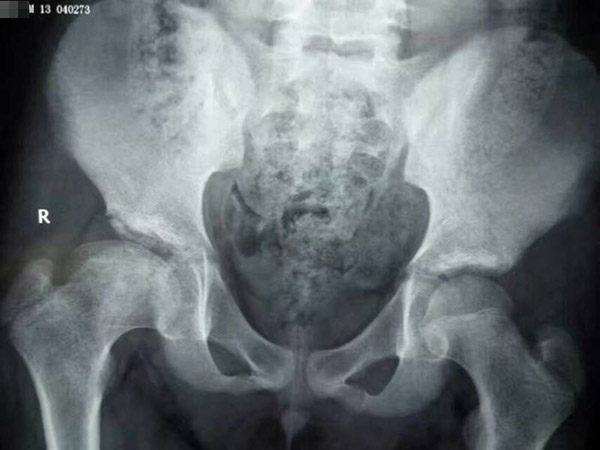

治疗前

治疗中

治疗后

在朋友的介绍下,亮亮的父母来到郑州中医骨伤病医院,经过不到两年的治疗,今年14岁的亮亮完已经全康复了。医生告诉他的父母,不用担心什么后遗症,现在亮亮好了完全是因为你们家长的这份心,如果不是当初的坚持,也不会有今天的结果。